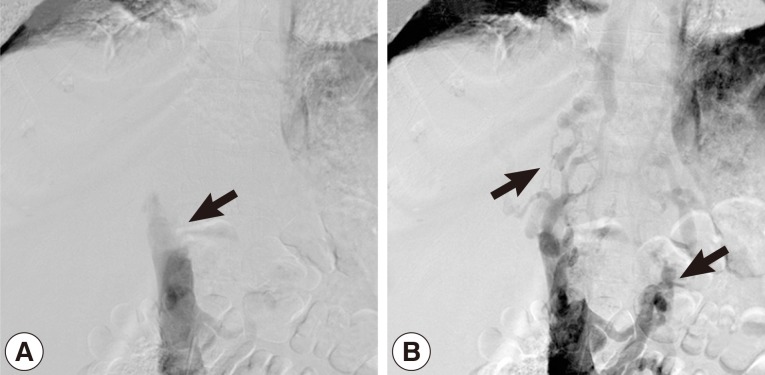

Hemoglobin was 8.3 g/dl in the whole blood count. Except for low albumin levels (2.1 g/dl), all other biochemical tests were normal. There was no flow viewed in the left hepatic vein and inferior vena cava on abdominal portal Doppler ultrasound. The portal vein was 16 mm, and the splenic vein was 15 mm in diameter and hepatofugal flow was noted. On contrasted abdominal CT, there was a 54×70×45 mm-sized cystic lesion in left lobe of the liver extending towards the posterior mediastinum with irregular calcifications that invaded the diaphragm, esophagus, and pericardium. It was occluding the inferior vena cava and left hepatic vein at the level where the hepatic veins poured into the inferior vena cava. Secondary to inferior vena cava occlusion, the azygos vein and the hemiazygos vein appeared to be dilated. There was bilateral pleural effusion (Fig. 1A, B). A grade 1 esophageal varix was observed on upper endoscopy. The inferior vena cava was found to be occluded at the L1 level with venography. It was determined that the venous return was provided by the azygos, hemiazygos system, and the collaterals (Fig. 2A, B). In the performed echocardiography, the entrance of the inferior vena cava into the right atrium was normal.